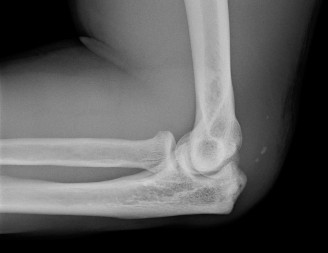

Understand the radiographic findings seen in patients with valgus overload? Identify indications for operative intervention? CASE 41 Dr. Min Lu A 14-year-old baseball pitcher presents to the office with left throwing elbow pain for the past two months when he throws or lifts weights. Examination reveals lateral joint line tenderness with no detectable effusion and full range of motion without crepitation. Moving valgus stress test does not elicit pain. His elbow radiograph is shown below (Fig. 2–111).

Figure 2–111

The correct answer is (E). This patient has osteochondritis dissecans (OCD) of the capitellum. He has not undergone any conservative treatment. Stable, nondisplaced lesions can heal spontaneously with rest and discontinuation of throwing. Surgical treatment is reserved for unstable lesions or loose bodies. This patient’s

examination is not consistent with an ulnar collateral ligament (UCL) injury. Little league elbow is another commonly encountered diagnosis in this patient population, but like UCL injuries, manifests with medial sided pain after throwing.